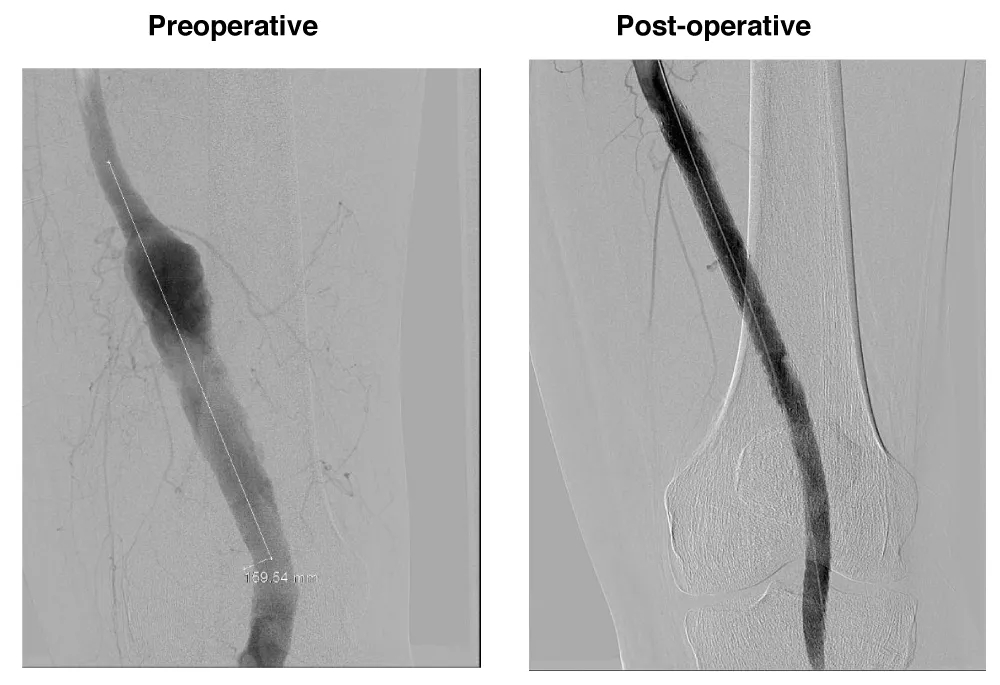

A male patient, 81 years, active smoker, with arterial hypertension and diabetes was admitted with right Lower limb distal microembolization, due to a 24 mm popliteal arterial aneurysm. The patient was submitted to endovascular surgery with the popliteal implant of endoprosthesis Wrapsody® 10x125 mm at distal neck, followed by an implant of Wrapsody 10x125 mm and Wrapsody 12x80 mm at proximal neck, followed by catheter balloon dilatation. (Figure 4).

Figure 4: Repair of a 24 mm popliteal artery aneurysm in an 81-year-old male with distal embolization: Preoperative image highlights microembolization signs and aneurysm. Postoperative angiogram demonstrates successful repair using three Wrapsody® endoprostheses (10×125 mm, 10×125 mm, 12×80 mm) with full restoration of patency and distal flow.

The patient was discharged from the hospital first day post-operative with Rivaroxaban 20 mg/day and a 1-month follow-up showed endoprosthesis patency with complete resolution of the previous symptoms.